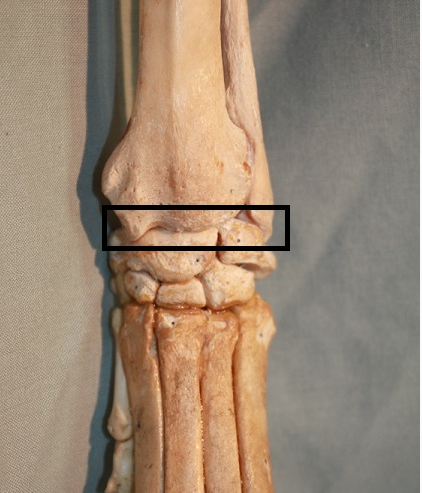

Antebrachiocarpal joint

Lateral coronoid process

A- radial carpal bone

B- 2nd carpal bone

Box?

Central tarsal bone

Red x- fourth tarsal bone